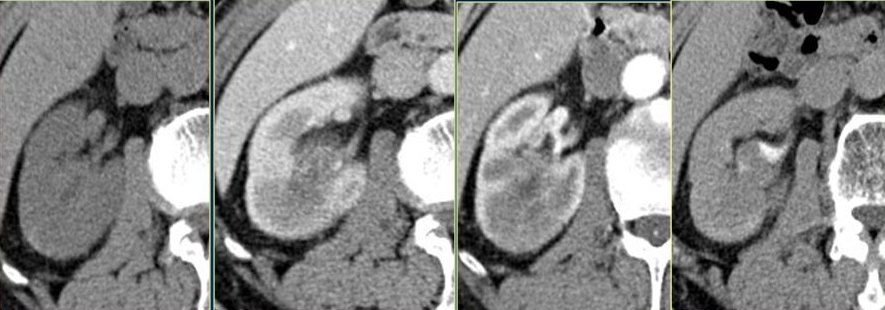

由于泌尿系统疾病的特殊性,绝大多数医疗机构的泌尿系CT,往往还有第四组片子,即“排泄期”,

? ? ? ? ? ? ? ? ? ? ? ? 平扫期? ? ? ? ? ? ? ? ? ? ? ? ? ? ? ? ? ? ? ? 实质期? ?? ? ? ? ? ? ? ? ? ? ? ? ? ? ? ? ? ? ?动脉期? ? ? ? ? ? ? ? ? ? ? ? ? ? ? ? ? ? ? ? ? 排泄期